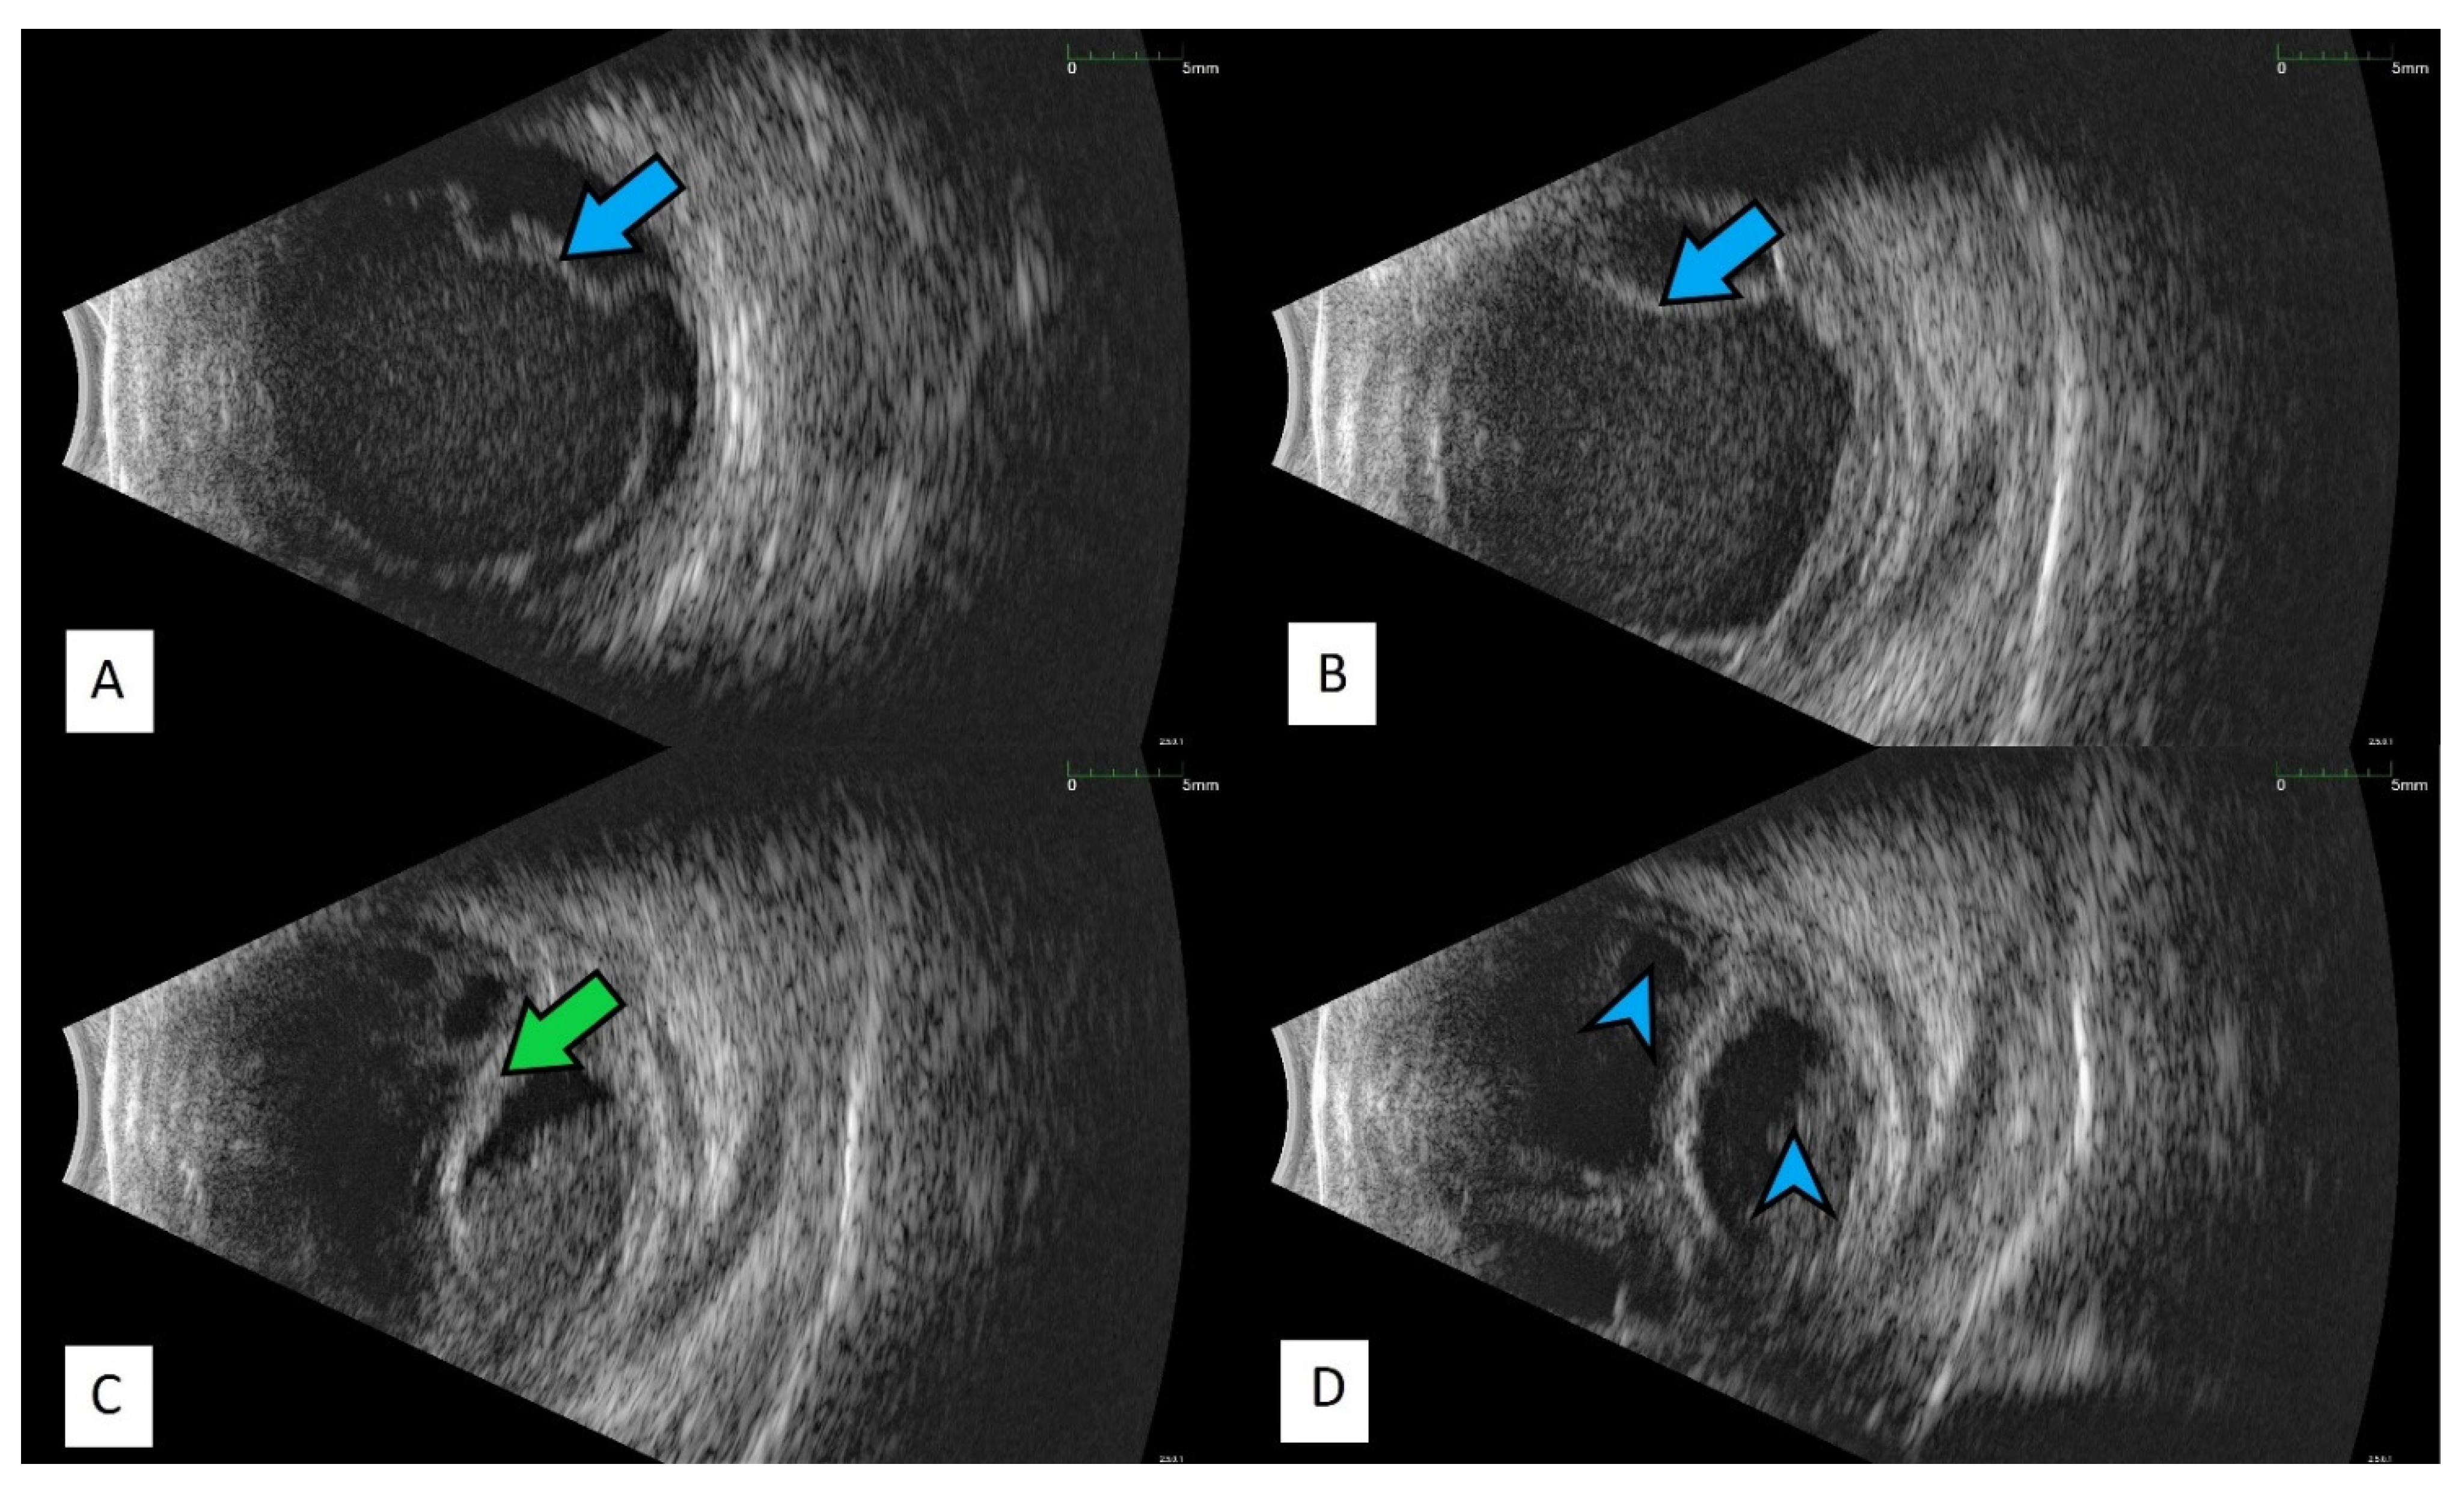

All of the above circumstances make the assessment of the vitreous body and retina in an ophthalmoscopic examination often impossible. The basic diagnostic tool in such cases is an ultrasound examination. Vitritis is inherent part of EE. Ultrasonography is nonspecific, however, it can indicate severity of the posterior involvement (Figure 6 and Figure 7) [80]. It also allows the assessment of the progression of changes (Figure 8). Features characteristic for EE include strands and membranes with reduced mobility (Figure 9). Other common changes are retinal detachment and subretinal abscess (Figure 10).

Figure 8.

Ultrasound B scans showing the evolution of changes during the development of inflammation. (A,B)—vitritis, posterior vitreous detachment (blue arrow), and retinal thickening. (C,D)—retinal detachment (green arrow) and numerous hyperechoic densities in the vitreous chamber (blue arrowhead).